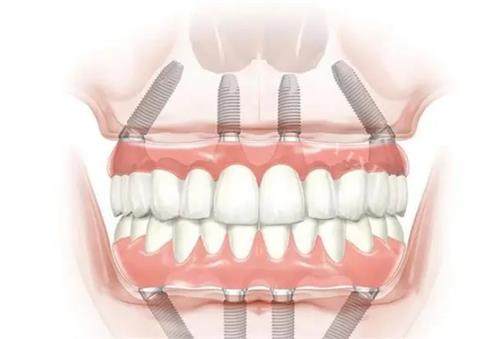

一、郑州美奥口腔种植牙价格参考

美国皓圣:3800元起

德国ICX:4500元起

德国Camlog:5200元起

瑞士ITI标准:6800元起

韩国登腾:2990元起

瑞典诺贝尔:7500元起

半口种植:3万元起

全口种植:5万元起